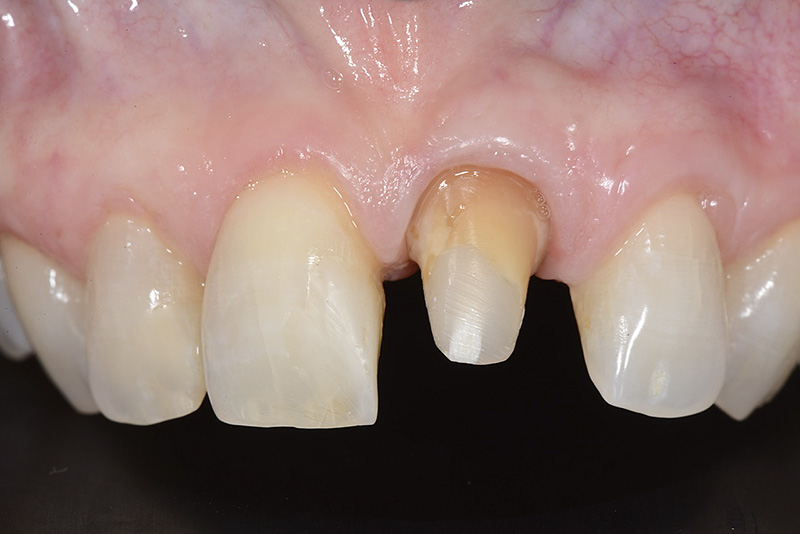

PREMESSA: in seguito all’estrazione dell’incisivo laterale superiore di destra, resasi necessaria per cause batteriche, si decide di affrontare il caso con il posizionamento di un impianto in sostituzione dell’elemento mancante dopo guarigione del sito infetto. Con tecniche rigenerative sia dei tessuti ossei mancanti a causa dell’infezione pregressa, sia dei tessuti gengivali che appaiono inizialmente troppo spostati in alto, si ripristina una corretta morfologia delle parabole (contorni) gengivali e delle papille interdentali (triangoli di gengiva tra due denti vicini).

Vengono utilizzati 2 tipi di provvisori: il primo, cementato ai denti vicini, viene utilizzato dal momento dell’estrazione del dente fino ad impianto osteointegrato (circa 6 mesi); il secondo, avvitato direttamente all’impianto, ha una funzione di prova estetica ma soprattutto di guida per la maturazione dei tessuti gengivali peri-implantari portandoli verso la maturazione completa prima di posizionare la corona finale in disilicato di litio.